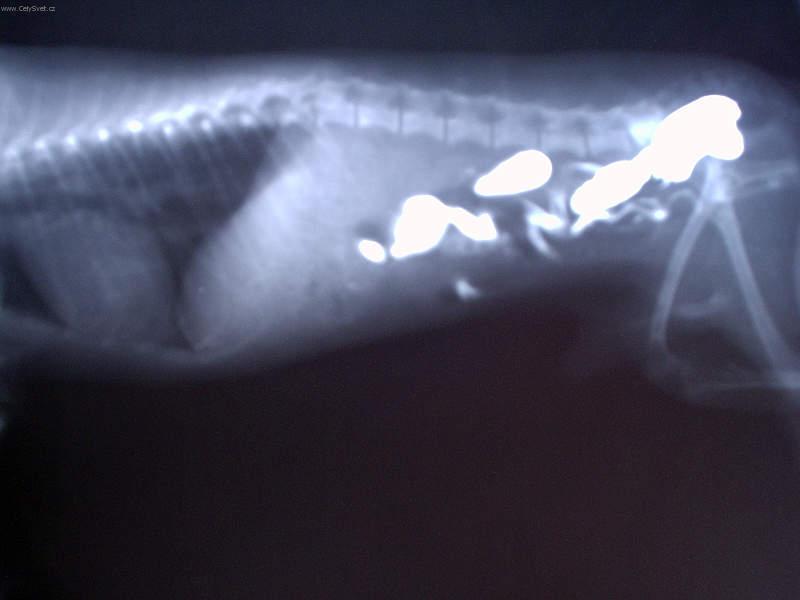

Fotogalerie > KOČIČÍ SVĚT: Veterinární poradna > Léčba interních onemocnění